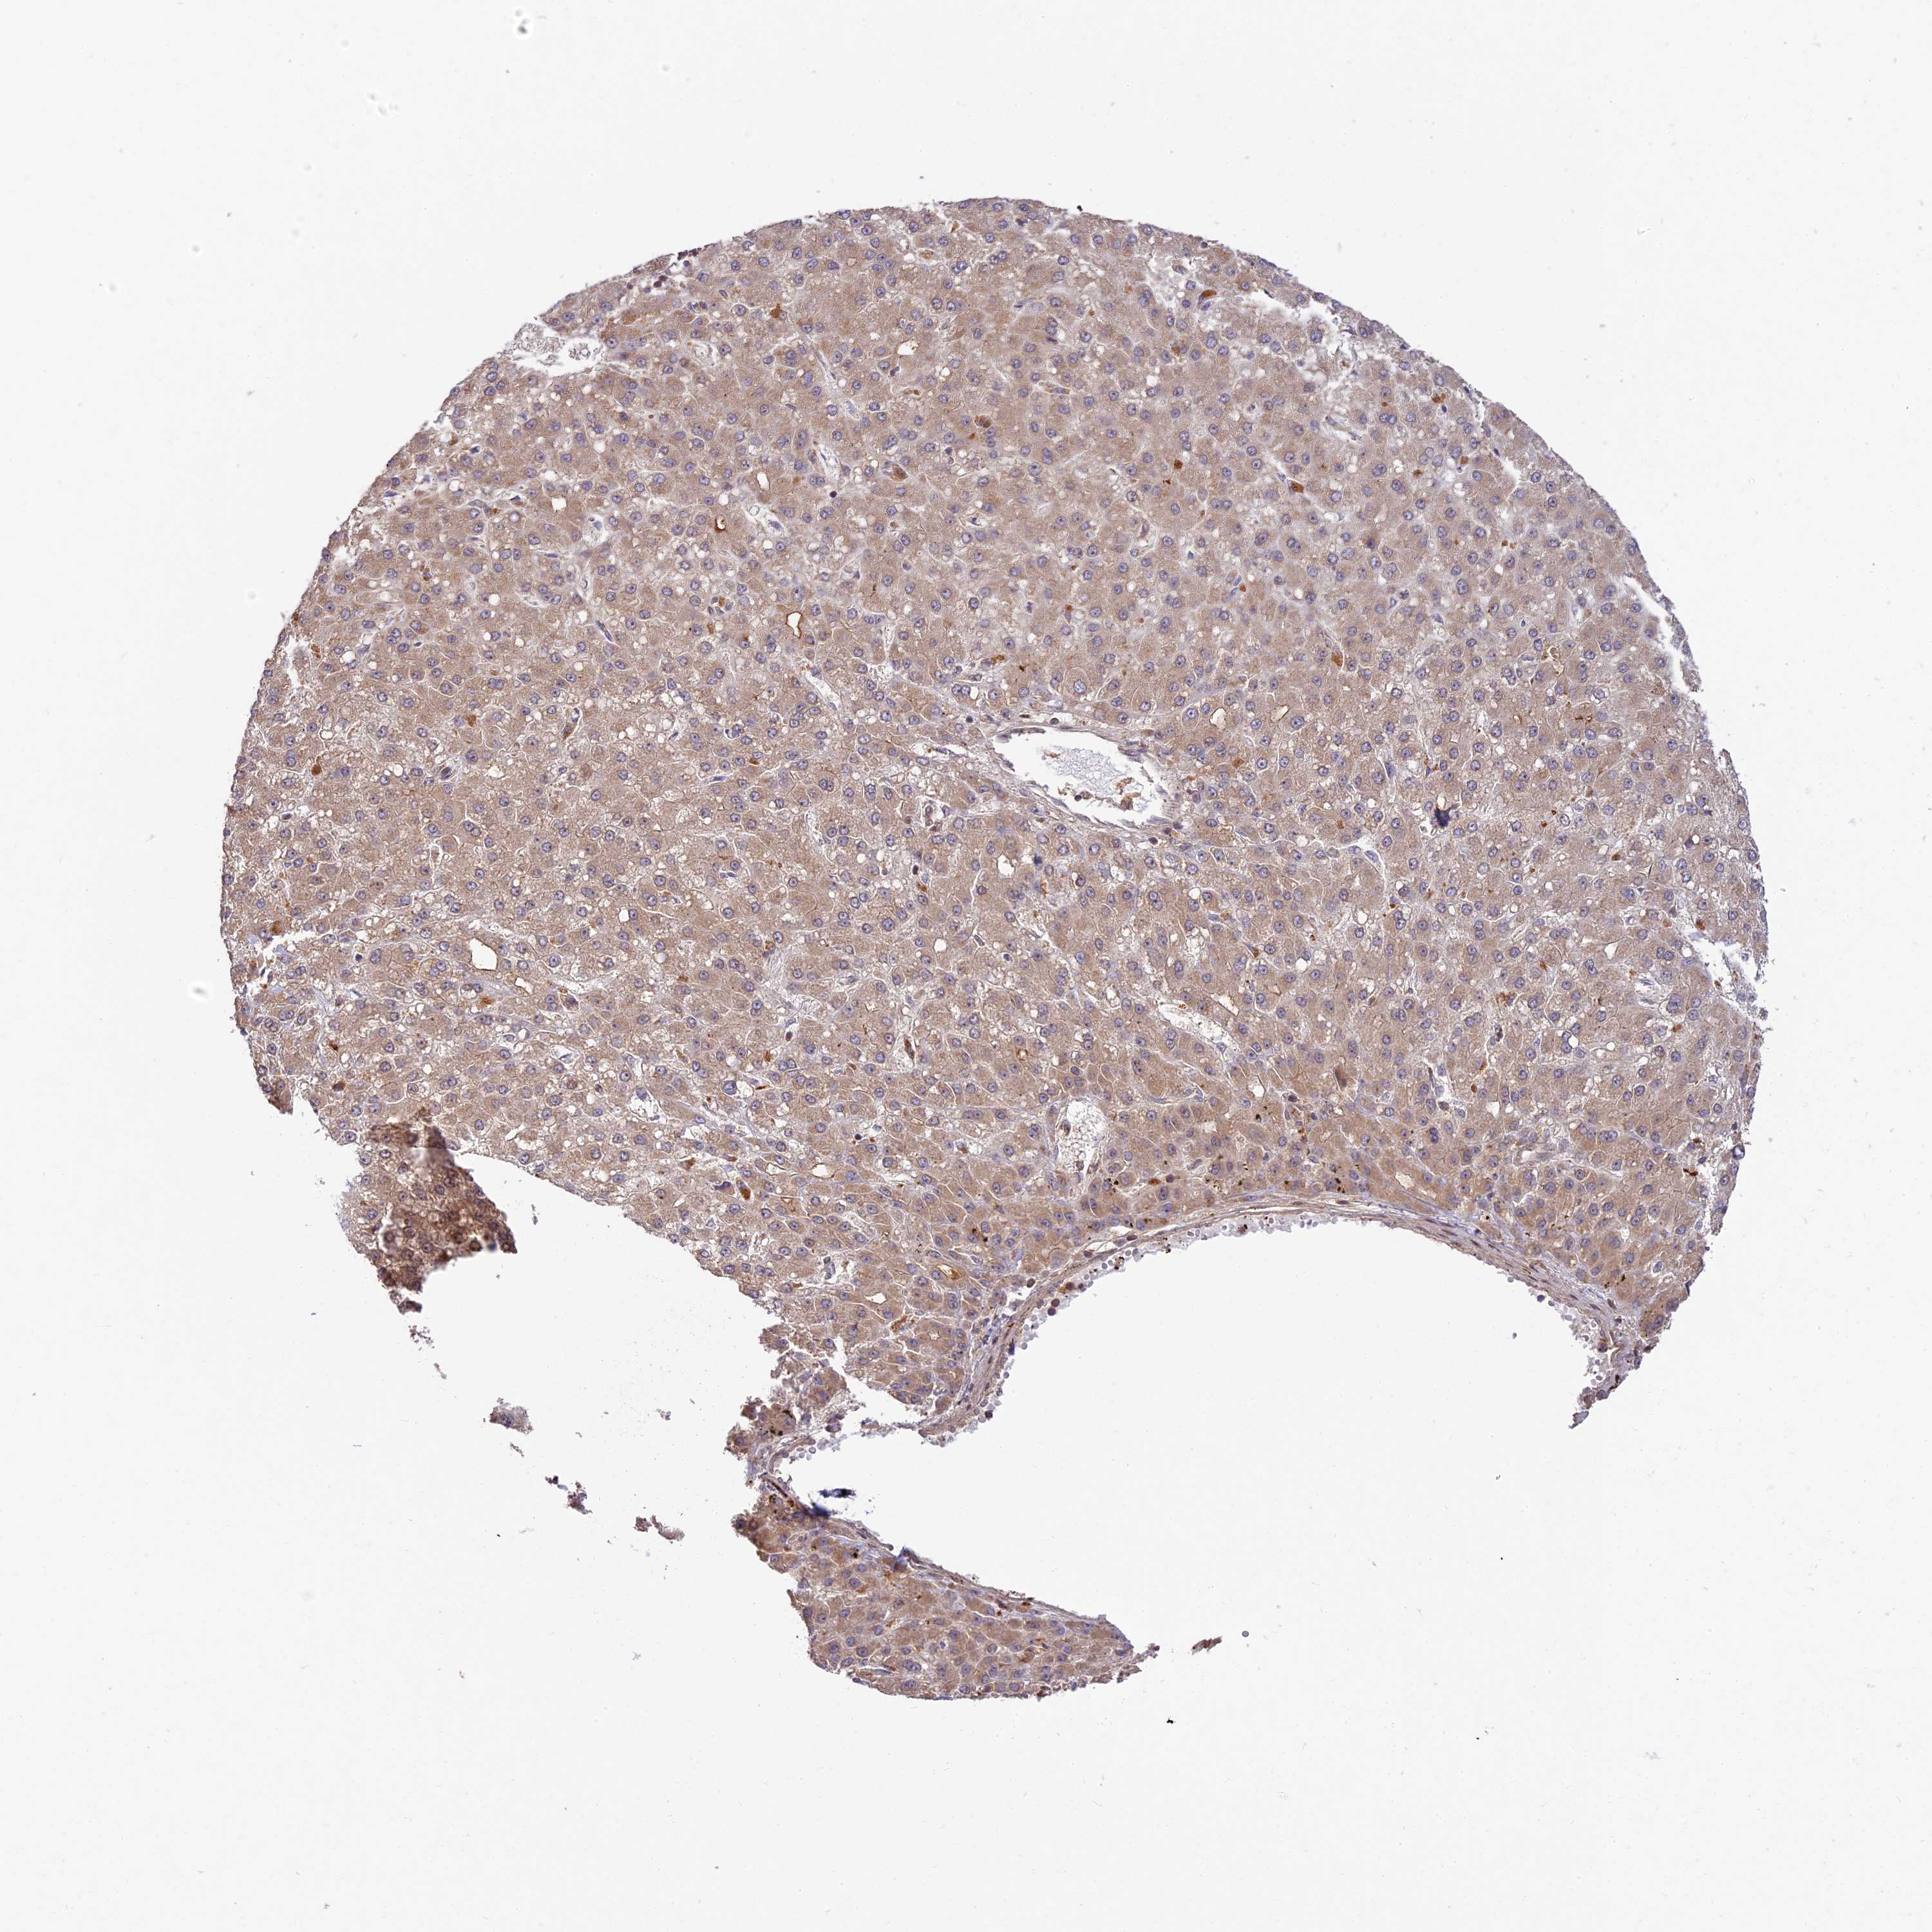

LIVER CANCER - Protein expressioni

A mouse-over function shows sample information and annotation data. Click on an image to view it in a full screen mode. Samples can be filtered based on level of antibody staining by selecting one or several of the following categories: high, medium, low and not detected. The assay and annotation is described here.

Note that samples used for immunohistochemistry by the Human Protein Atlas do not correspond to samples in the TCGA dataset.

Antibody stainingi

Antibody staining in the annotated cell types in the current human tissue is reported as not detected, low, medium, or high, based on conventional immunohistochemistry profiling in selected tissues. This score is based on the combination of the staining intensity and fraction of stained cells.

Each image is clickable and will lead to virtual microscopy that enables deeper exploration of all samples and also displays staining intensity scores, fraction scores and subcellular localization as well as patient and tissue information for each sample.

Antibody HPA039533

Antibody HPA040355

Staining

High

Medium

Low

Not detected

Intensity

Strong

Moderate

Weak

Negative

Quantity

>75%

75%-25%

<25%

None

Location

Nuclear

Cytoplasmic/membranous

Cytoplasmic/membranous,nuclear

Cholangiocarcinoma

Carcinoma, Hepatocellular, NOS